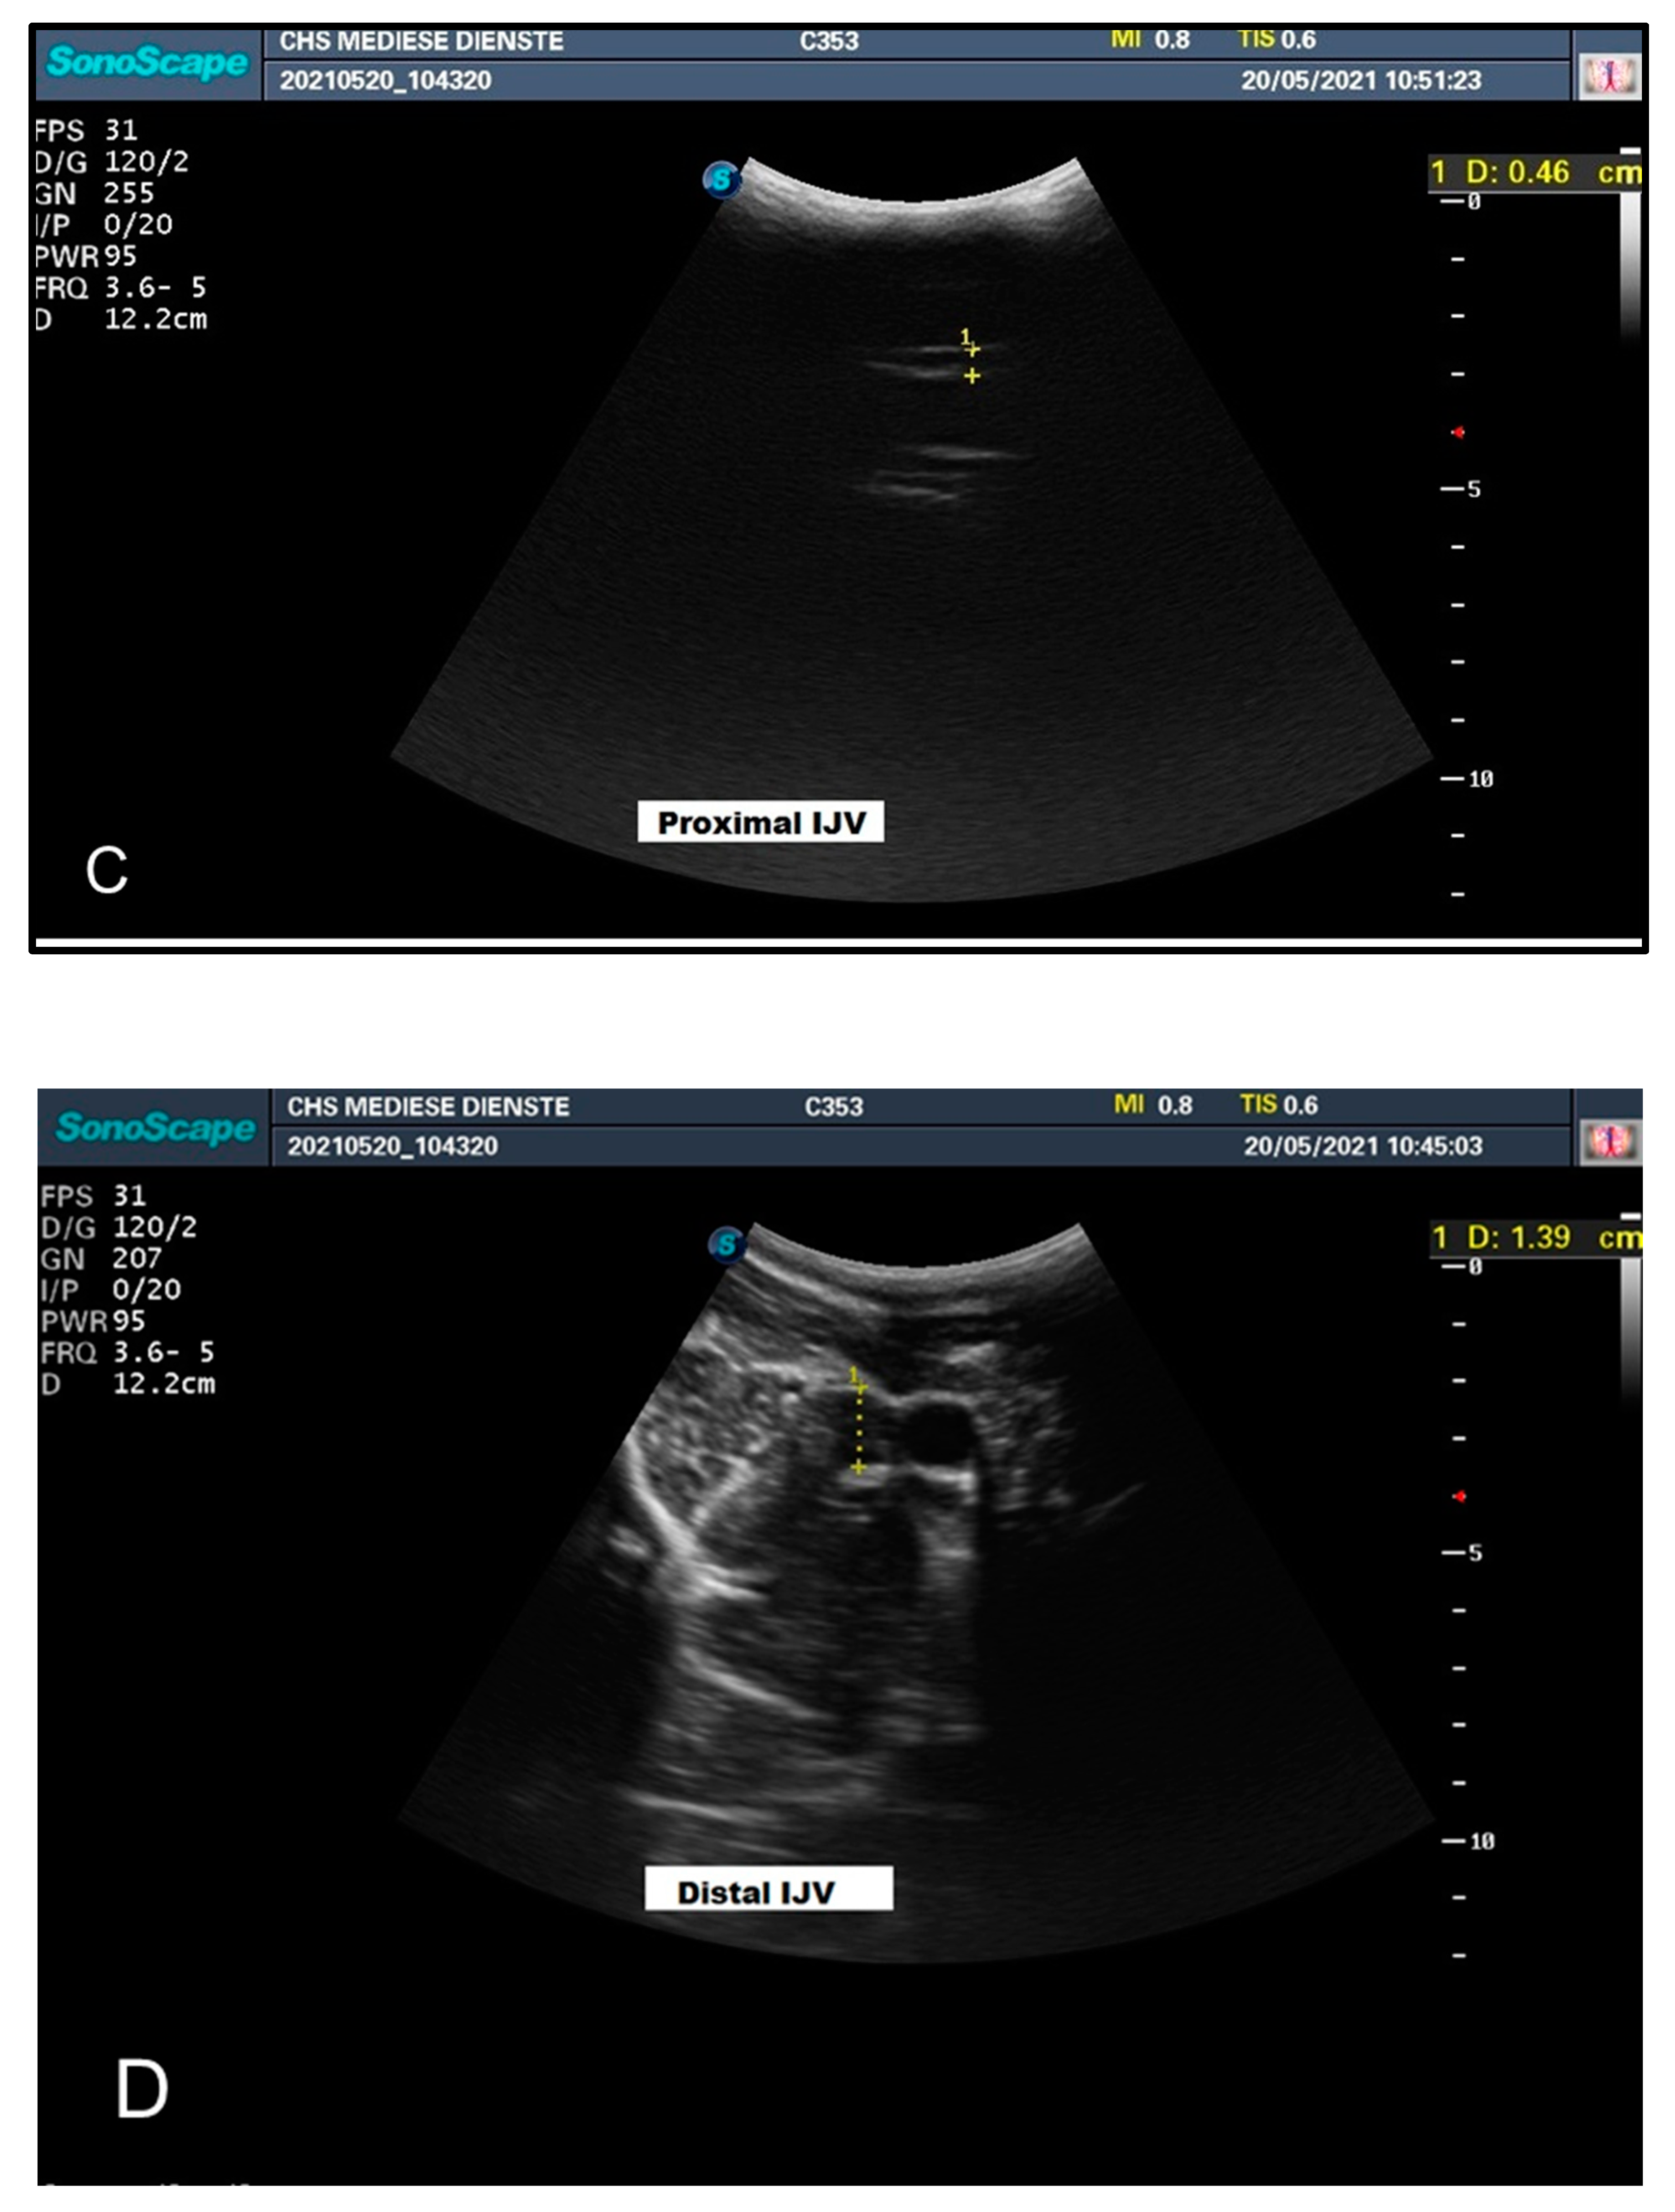

| Head Position | Diameter (mm) CCA | Diameter (mm) IJV | ||

|---|---|---|---|---|

| Proximal | Distal | Proximal | Distal | |

| Head Up | 13.8 | 13.9 | 4.6 | 13.9 |

| Head Down | 13.1 | 13.3 | 12.6 | 16.1 |